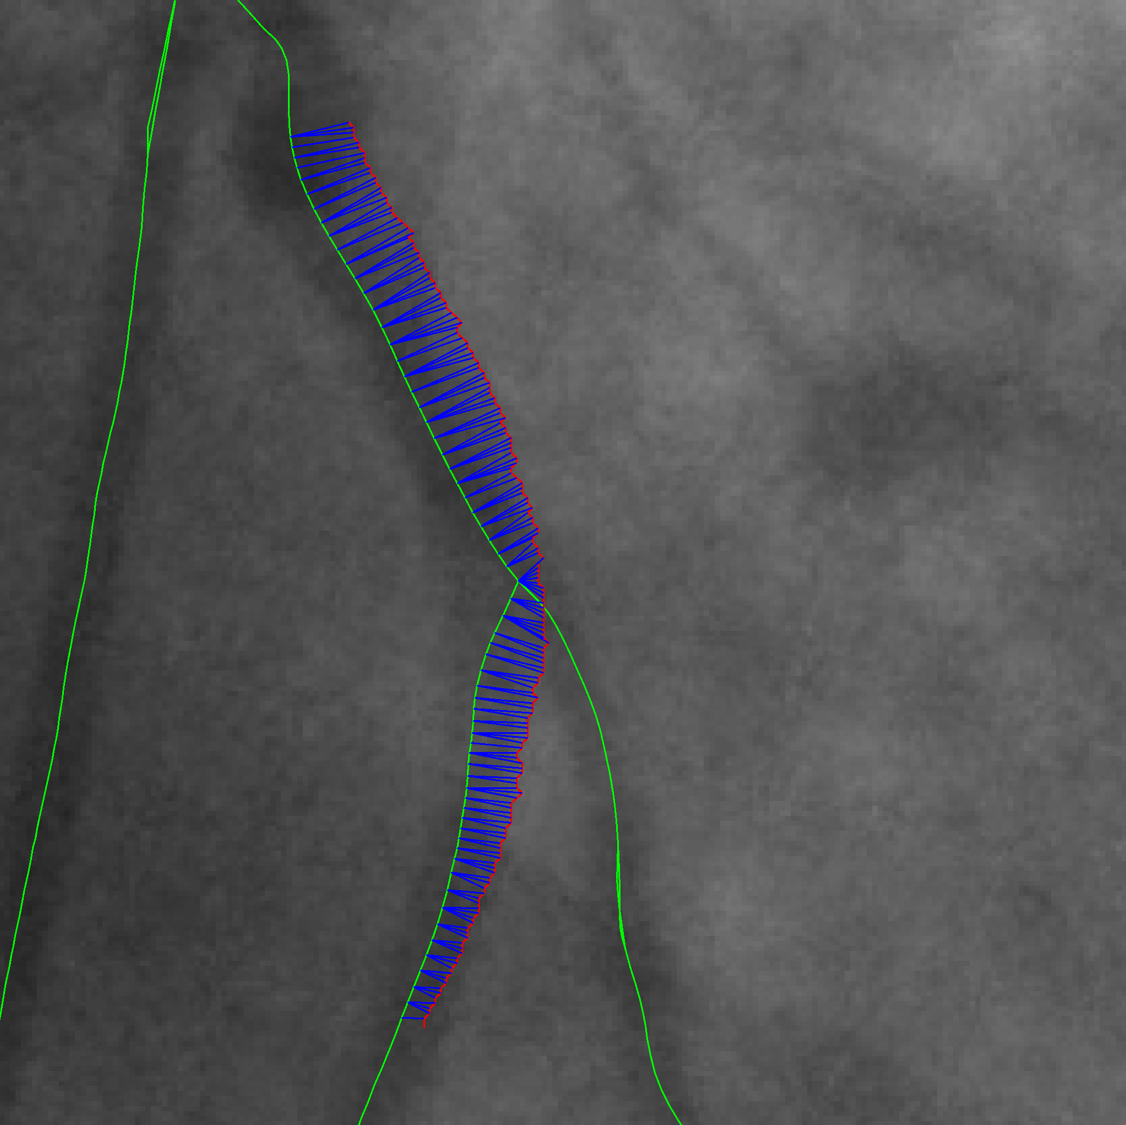

Figure 1: VOIDD: (from left to right)Input image f𝑓f; centerline of segmented guidewire tip; tip candidate (red) matched to vessel centerline (green) marked by pairings(blue); corresponding location (green) of guidewire tip(red) inside vessel.

Tip candidate extraction. Guidewire tip appears as contrasted thin and elongated object in the fluoroscopic image. We are interested to segment the guidewire tip, using a component tree called min tree. The min tree [9] structures all the connected components of the lower-level sets of the grayscale image based on inclusion relationship. We assign to any connected component C𝐶C of the min tree \mathcal{M}, a shape attribute characterizing the shape and structural properties of guidewire tip. Then, the considered attribute 𝒜𝒜\mathcal{A} describes the elongation of the components. For any component C𝐶C𝒜(C)=(π×lmax(C)2)/|C|,𝒜𝐶𝜋subscript𝑙𝑚𝑎𝑥superscript𝐶2𝐶\mathcal{A}(C)={(\pi\times{l_{max}(C)}^{2})}/{|C|}\enspace, where |.||.| represents cardinality and lmax(C)subscript𝑙𝑚𝑎𝑥𝐶l_{max}(C) is the length of the largest axis of the best fitting ellipse for the connected component C𝐶C. Since the guidewire tip is thin and long, the component corresponding to the tip have high value of attribute 𝒜𝒜\mathcal{A}. A mere thresholding of the elongation 𝒜𝒜\mathcal{A} is not sufficient, often giving other long and elongated (unwanted) objects like pacing lead and filled catheters. Indeed, these objects have higher elongation value than the guidewire tip. Hence, according to physical properties of the guidewire tip, we set a upper bound value tmaxsubscript𝑡𝑚𝑎𝑥t_{max} on 𝒜𝒜\mathcal{A} to maximum possible elongation value of the guidewire tip, to ensure that extracted components contain guidewire tip. Even with this upperbound threshold keeping the most elongated component does not always lead to the desired tip. Based on min tree structure, the nested connected components that satisfy the criterion are filtered to preserve the component with largest area (taking aid of the inclusion relationship). Therefore, we adopt the shaping framework [10] that allows us to efficiently extract significant connected components. The extracted components constitute the tip candidates. Shaping extensively uses the min tree structure to regularize the attributes and to select the relevant components. In order to facilitate matching, we perform skeletonization [3] of the selected connected component(s) to obtain centerline of the tip candidates. Fig. 1 shows the obtained centerline of segmented guidewire tip from the input image. This centerline of the tip candidate 𝒞𝒞\mathcal{C} is modeled as a discrete polygonal curve.

Matching. An important step in the task of vessel-of-intervention detection is to designate possible desirable associations of the corresponding location of the guidewire tip inside the injected vessel. We refer to these locations in vessels as vessel-of-interest (VOI) candidates. This step refers to building the correspondences between the centerline of each tip candidate 𝒞𝒞\mathcal{C} extracted from navigation sequence and the corresponding centerlines of the vessels 𝒳𝒳\mathcal{X} extracted from reference sequence by taking into account ECG information. We adopt the curve pairing algorithm of [2] to perform this task. It is required to define a curve-to-curve distance to compare the two sets of curves mentioned above. We use a discrete version of Fréchet distance [1] as it takes into account the topological structures of the curves. Thus, this Fréchet distance is computed from a mapping between two ordered sets of discrete polygonal curves denoted by 𝒞𝒞\mathcal{C} and by XCsubscript𝑋𝐶X_{C}, respectively. Imposed non-decreasing surjective mappings (reparameterization mapping) in computation of Fréchet distance takes into account the order of points along curves. This order also helps us in curve pairing described below, to give scan direction along the curves.

The above step requires the selection of every admissible curve XCsubscript𝑋𝐶X_{C} in graph 𝒳𝒳\mathcal{X}. A curve in 𝒳𝒳\mathcal{X} is a path between two nodes, without visiting the same edge twice. In order to restrict computational complexity of search, we restrict the set of admissible curves to be in the neighborhood of the tip candidate extremities 𝒞[1]𝒞delimited-[]1\mathcal{C}[1] and 𝒞[n]𝒞delimited-[]𝑛\mathcal{C}[n] and we construct all possible paths between them in the graph. Indeed, these admissible curves are the VOI candidates. These VOI candidates, together with the tip candidate 𝒞𝒞\mathcal{C}, is a set of feature pairs 𝒫={(𝒞,XC)XC\mathcal{P}=\{(\mathcal{C},X_{C})\mid X_{C} is some curve in 𝒳𝒳\mathcal{X} matched to 𝒞}\mathcal{C}\}, which are further filtered and ranked according to the shape similarity measure to prefer VOI candidates with higher shape resemblance to the tip candidate. This term is computed from residual Fréchet distance after the 2D transformation [2]. The set of feature pairs 𝒫𝒫\mathcal{P} is computed for each image in the guidewire tip navigation sequence by performing the matching with the vessel graph of the corresponding cardiac phase.